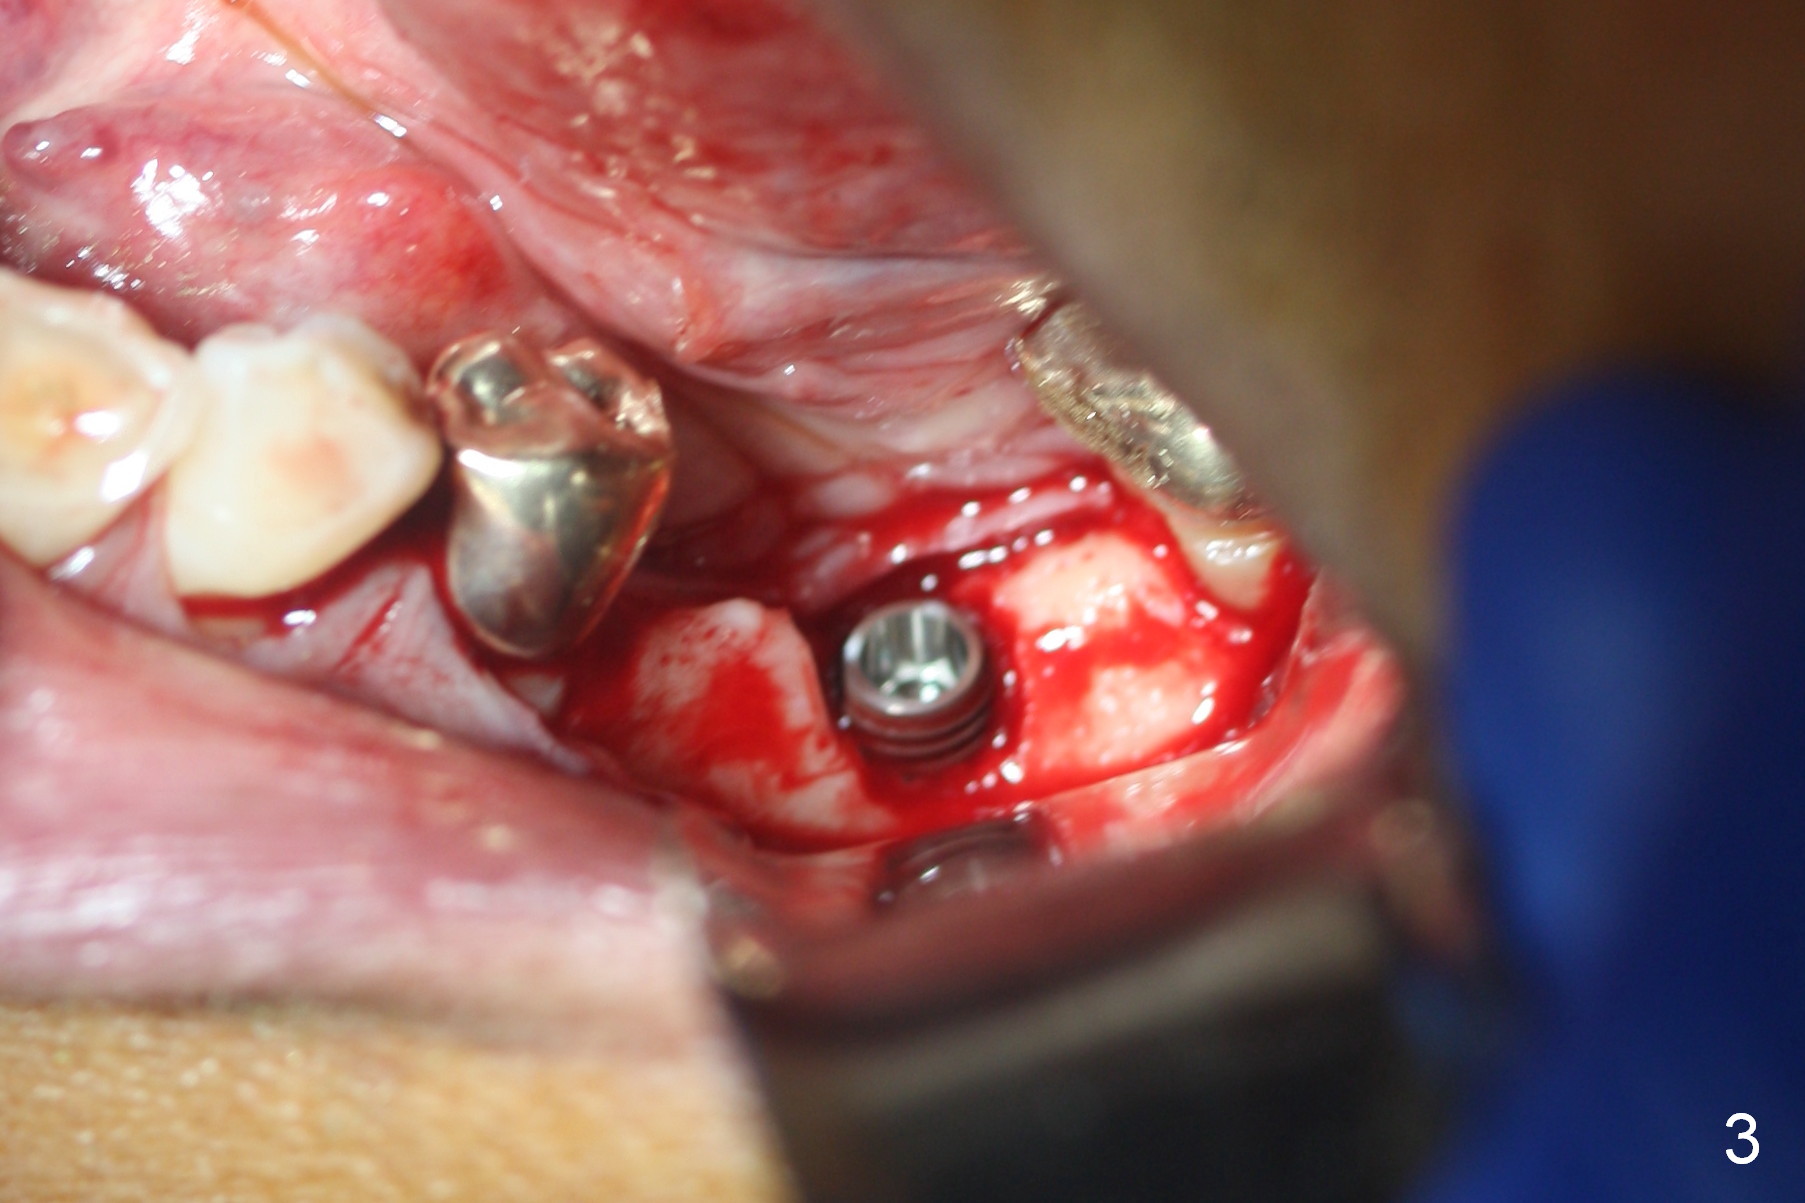

The narrow ridge top is trimmed until the buccolingual width is 7-8 mm; osteotomy starts in the flattened ridge (Fig.1, 2). A 5x10 mm implant is being placed (Fig.3). A cemented abutment (6.5x5.5(5) mm) is placed after adjusting the mesial and distal walls of the trimmed ridge (Fig.4). The patient returns for restoration 6 months postop. The coronal opening of the osteotomy becomes flared (Fig.5). The position and trajectory of the osteotomy should have been changed as early as possible (Fig.6, more or less parallel to the premolar) to avoid necessity of changing the cemented abutment (Fig.7 (* keratinized gingiva)) to an angled one (5.5 x15 degree A (4) mm).